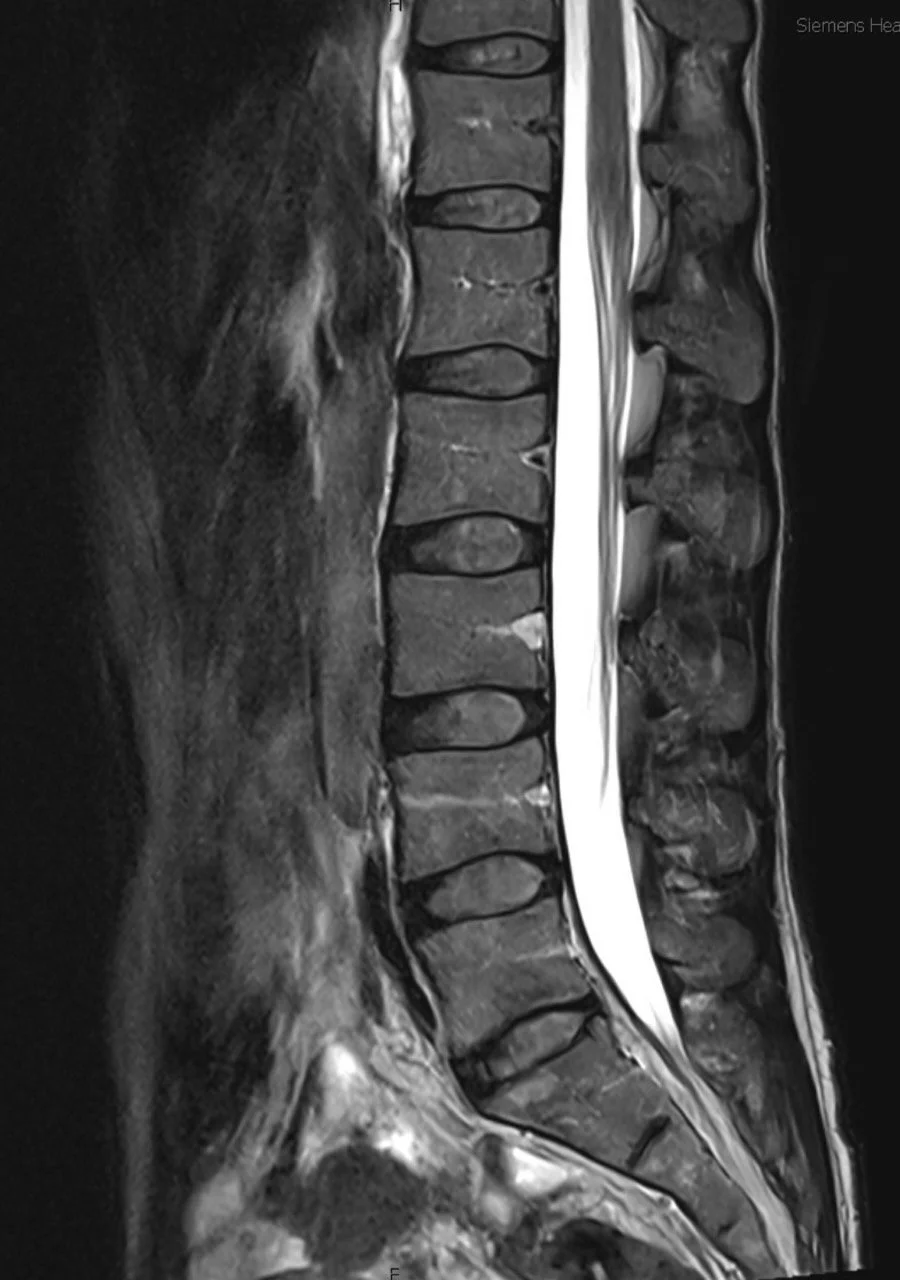

Spinal Column and Spinal Cord Spinal Column Learn More Spinal Cord Learn More Cervical Spine Learn More Lumbar Spine Learn More